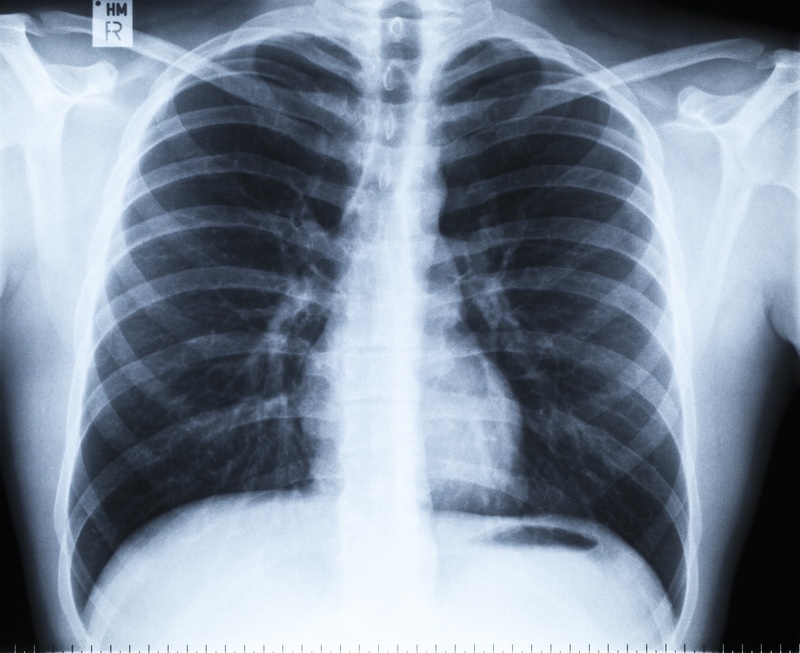

AIを用いた診療支援を実現するために蓄積すべきデータの中でも、私が最も重視しているものは放射線画像などの画像データです。

厚生労働省では、平成28年度から日本医療研究開発機構を通じて、放射線画像などの医療画像を集める事業を実施しています。

AIを用いた精度の高い画像診断(X線、CT、MRIなどの画像による病気の発見や早期診断)は、ディープラーニングと呼ばれる技術の革新により、早期に実用化できるものと期待されています。

現在は、画像診断を実現するために有用な画像データとは一体どのようなものか、また、その画像データをどのような方法で収集・蓄積していくかを議論することが重要です。